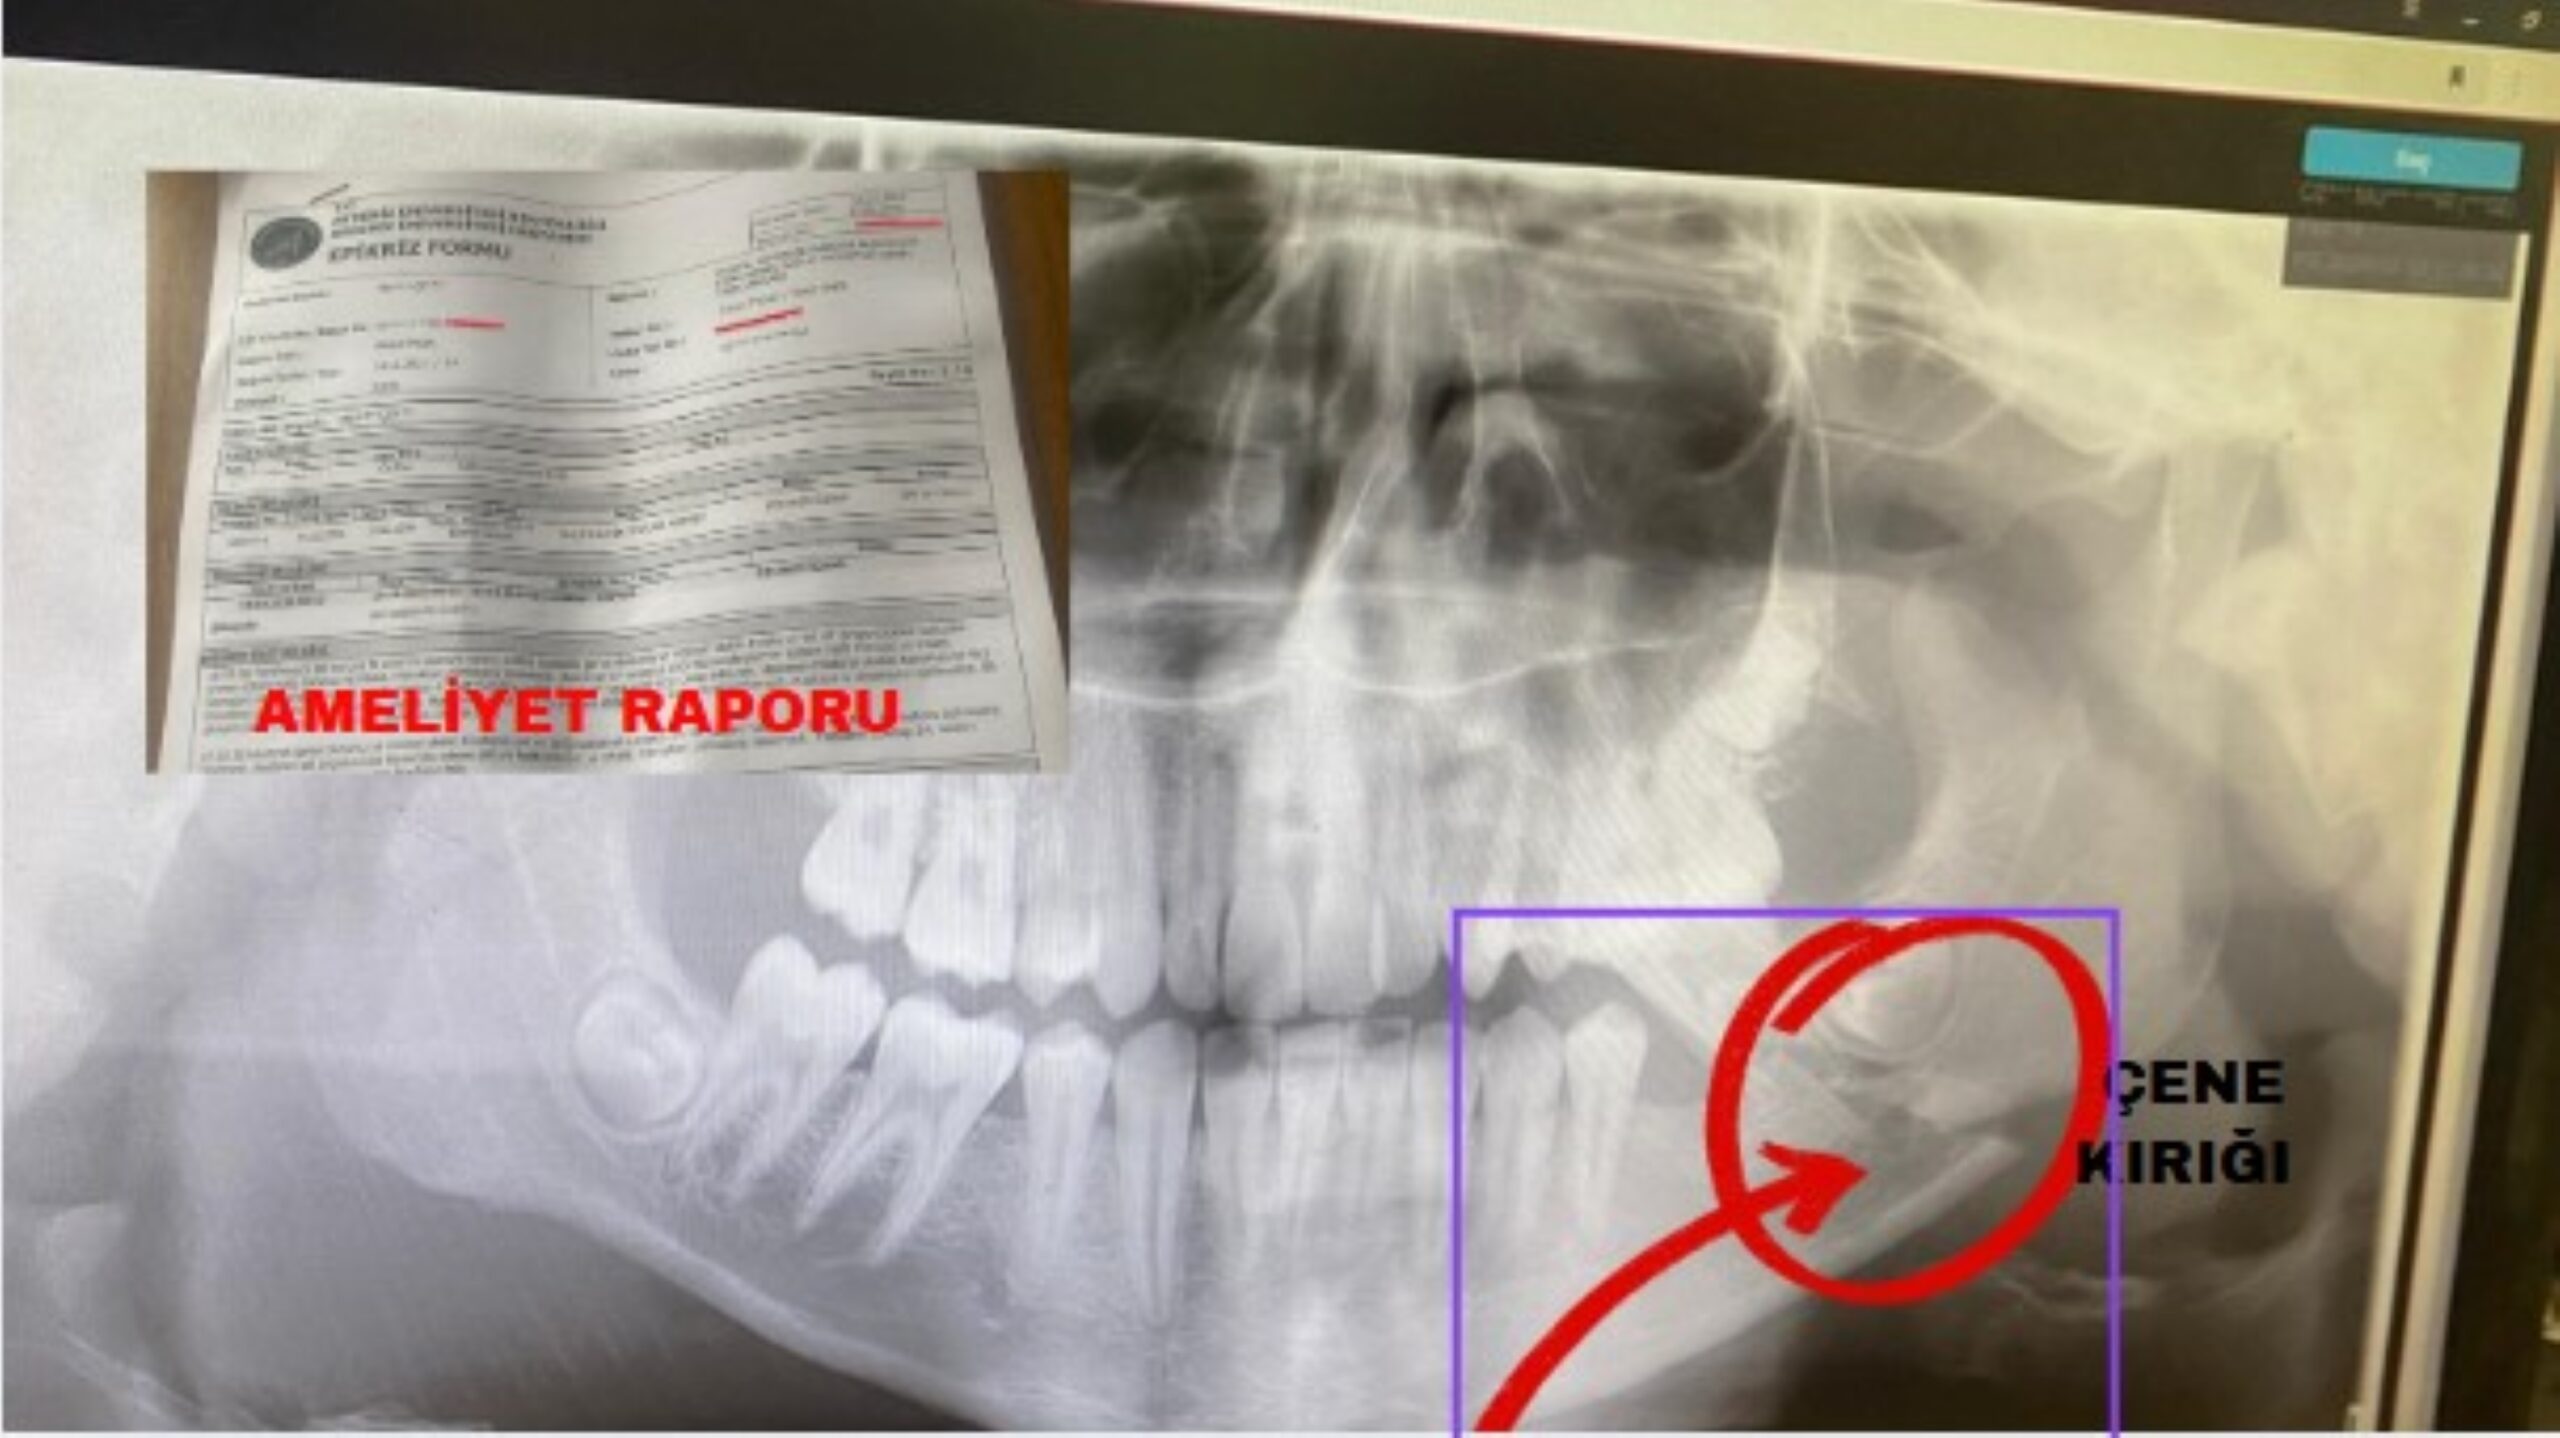

Kepez ilçesinde bir okulda öğrencinin uzun süreli zorbalığa maruz kaldığı ve olayların taciz boyutuna ulaştığı iddia edildi. Muratpaşa’da yaşanan olayla ilgili konuşan veli, öğrencinin sınıf içinde darp edilerek çenesinin kırıldığını söyledi. Velinin iddiasına göre, başka bir sınıftan gelen öğrenciler tarafından saldırıya uğradı. Hastaneye götürülen öğrencinin çenesinde kırık tespit edildi. Yaralı öğrenci Akdeniz Üniversitesi Çene Cerrahisi bölümünde ameliyat geçirdi.